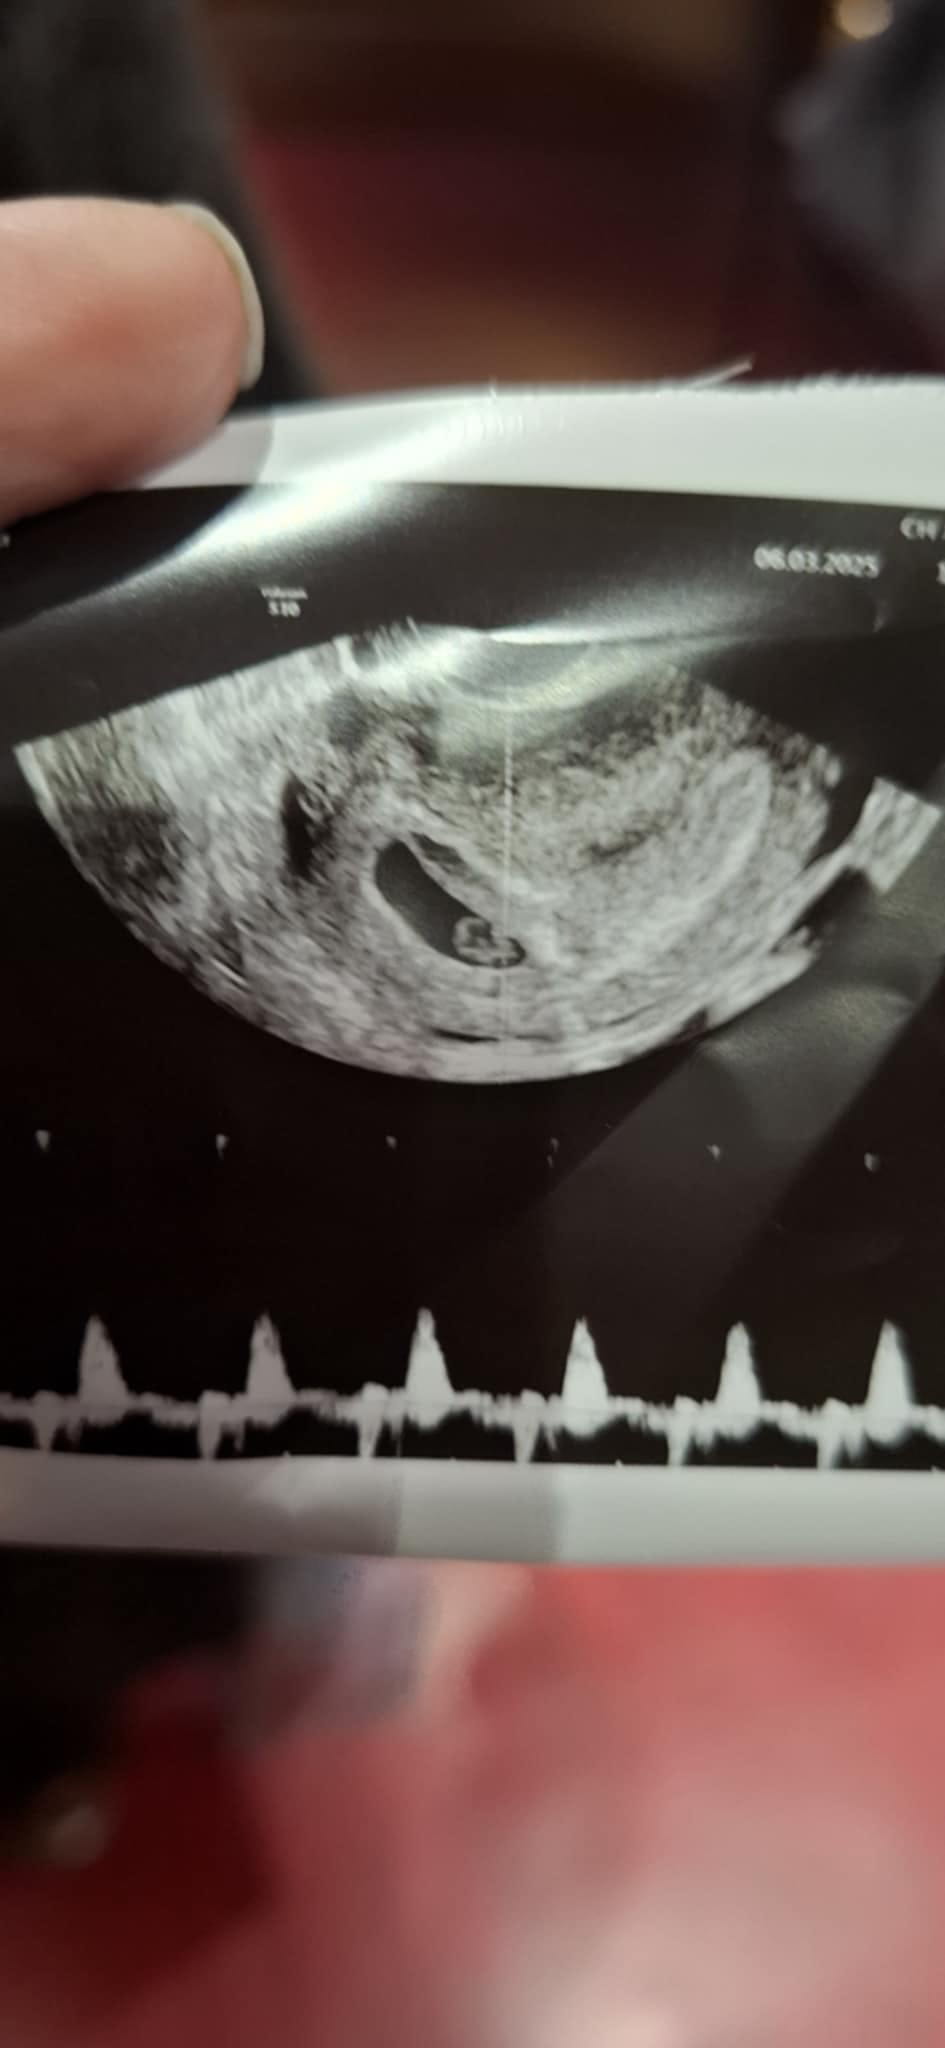

- Ventre jumeaux 1 mois grossesse - Accueil - Questions de femme enceinte

- Test de grossesse 2 barre foncée jumeaux - Accueil - Questions de femme enceinte

- Grossesse intra uterine - Accueil - Maux de la grossesse